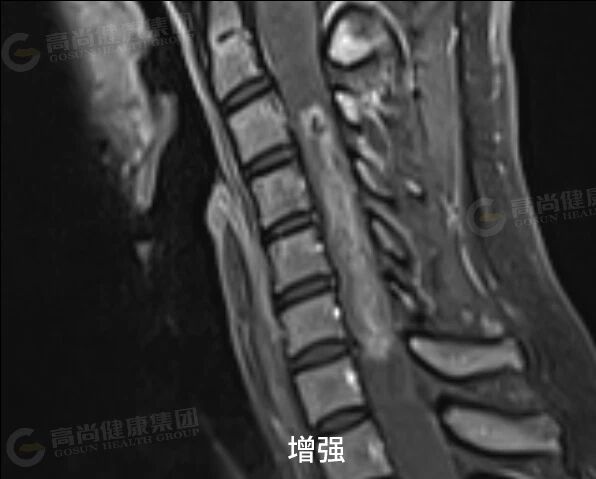

女性,34 岁,外院诊断脊髓空洞,走路失稳伴肢体麻木,来中心增强检查。

延髓水平至 T12 椎体水平椎管内可见分布大小不等囊状信号,C2 椎体下缘水平至 C7 椎体水平下缘髓内可见长 T1、混杂长 T2 信号,病灶两端见弧形低信号,T2 压脂示病灶内散在结节状稍高信号,横轴位见肿块位于脊髓中央,正常脊髓显示不清,增强扫描呈轻中度不均匀强化,范围约 73 mm×15 mm。

结论:颈髓内占位伴广泛性脊髓囊样改变,考虑室管膜瘤伴脊髓空洞可能。

增强扫描特征: 绝大多数(>95%)室管膜瘤明显强化。强化模式多样:可呈均匀、不均匀或环状强化。强化边界通常清晰,有助于划定肿瘤范围。